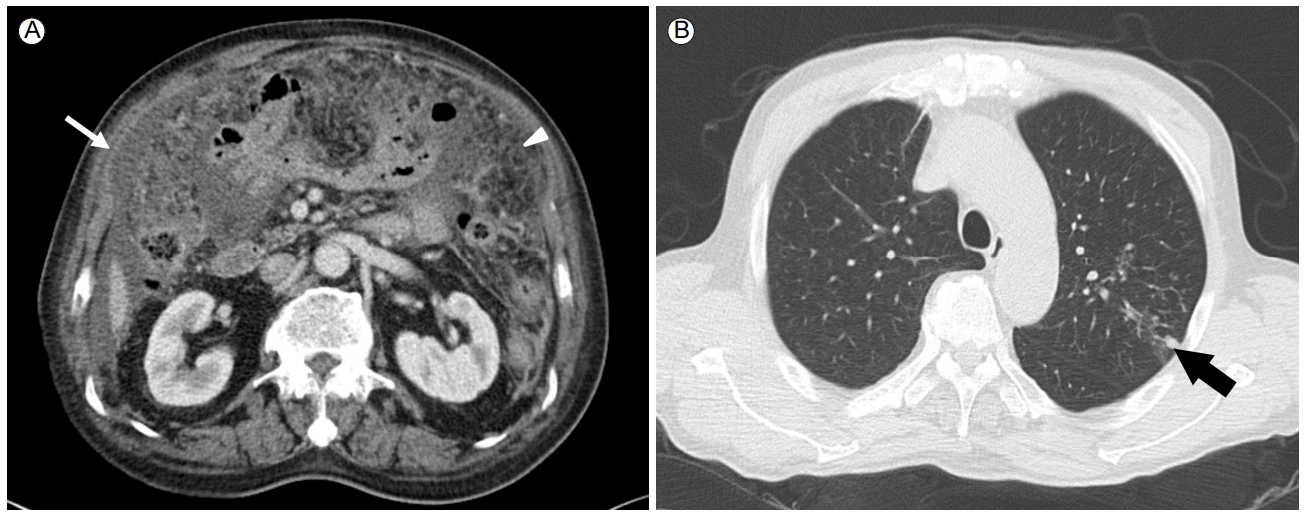

An abdominal computed tomography (CT) scan revealed massive ascites, peritoneal thickening, and a smudged appearance of the omentum (Fig. 2A). The ascites contained 2,560/mm3 white blood cells with 40% lymphocytes, and elevated adenosine deaminase (ADA) at 97.4 IU/L (normal, < 40 IU/L). Ascites cultures for bacteria and Mycobacterium tuberculosis and cytology results were negative. Sputum cultures were also negative for M. tuberculosis.

Computed tomography. (A) Abdominal CT revealed massive ascites, peritoneal thickening (thin arrow), and a smudged appearance of the omentum (arrowhead). (B) Chest CT revealed a small infiltrative lesion (thick arrow) in the left upper lobe.

Although the chest x-ray revealed no active lung lesions, we performed chest CT to identify the site of primary infection, which revealed a small infiltrative lesion in the left upper lobe (Fig. 2B). Bronchoscopy showed no endobronchial lesions. No acid-fast bacilli were seen, and PCR of the sputum for M. tuberculosis was negative, while PCR of the bronchoalveolar lavage fluid was positive.